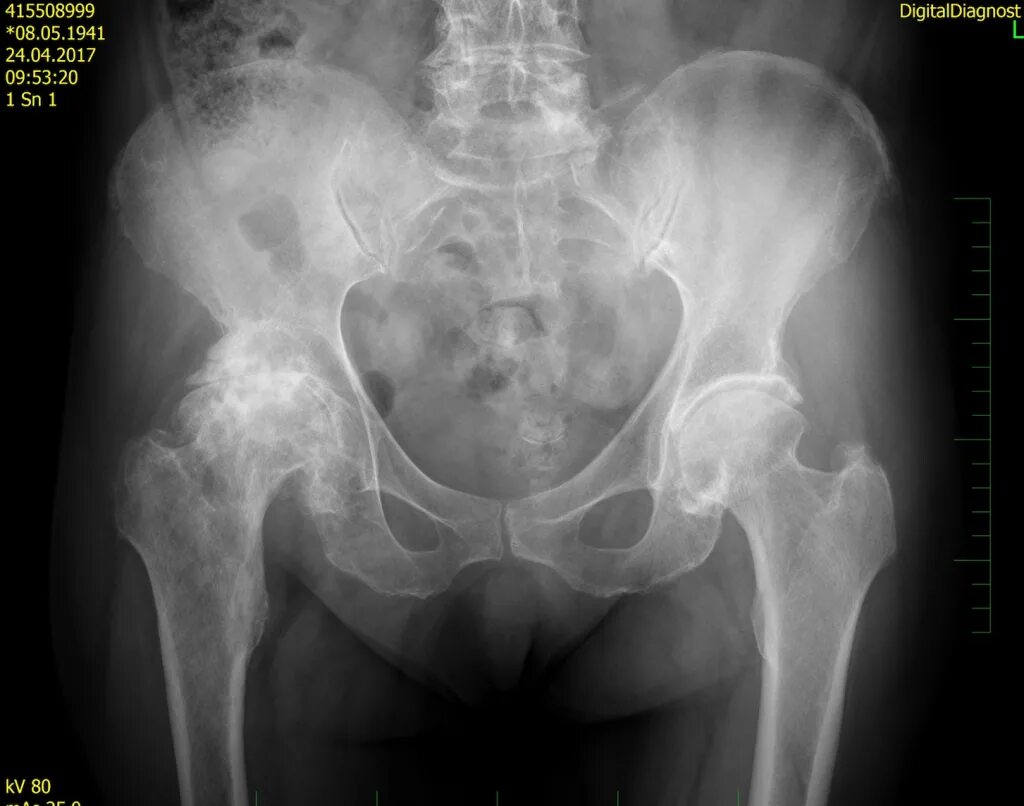

Деформирующий остеоартроз тазобедренных суставов 1 степени